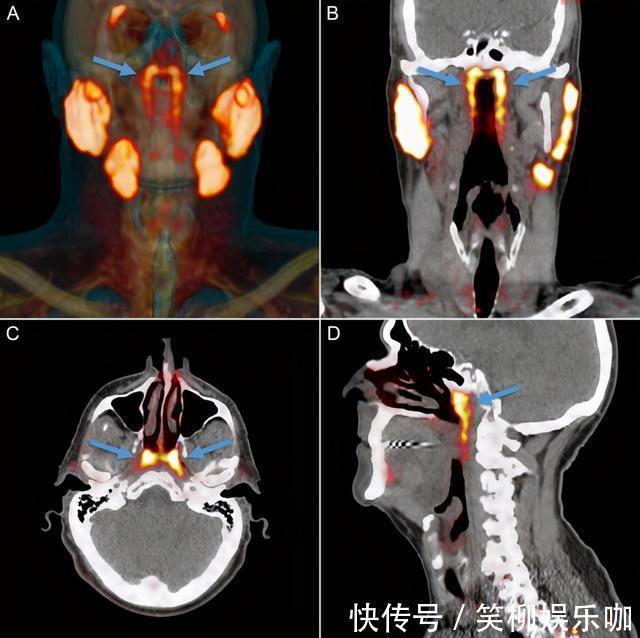

【摘 要】:达尔文的进化论时总被很多人诟病,因为没有人见证过人类自己进化的过程,所以无论提出多严谨的证据,相信人类在继续演化的事实依然只有理性派科学人士。 但最近发表于《解剖学

达尔文的进化论时总被很多人诟病,因为没有人见证过人类自己进化的过程,所以无论提出多严谨的证据,相信人类在继续演化的事实依然只有理性派科学人士。